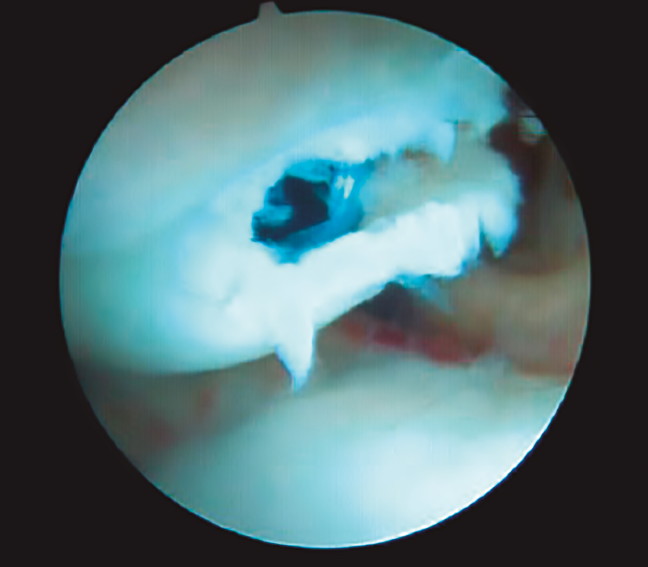

Para reducir el tiempo de inmovilización en las fracturas no desplazadas, se ha propuesto la realización de una TC a las 4 semanas de la fractura, considerando que si se evidencian puentes óseos puede iniciarse la movilización de la muñeca, retirando la inmovilización; se aconseja, si estos no están presentes, la realización de una síntesis percutánea del escafoides(14), ya que se considera que no consolidará (Figura 2).

Figura 2. Tomografía computarizada a las 4 semanas donde se evidencian puentes óseos.